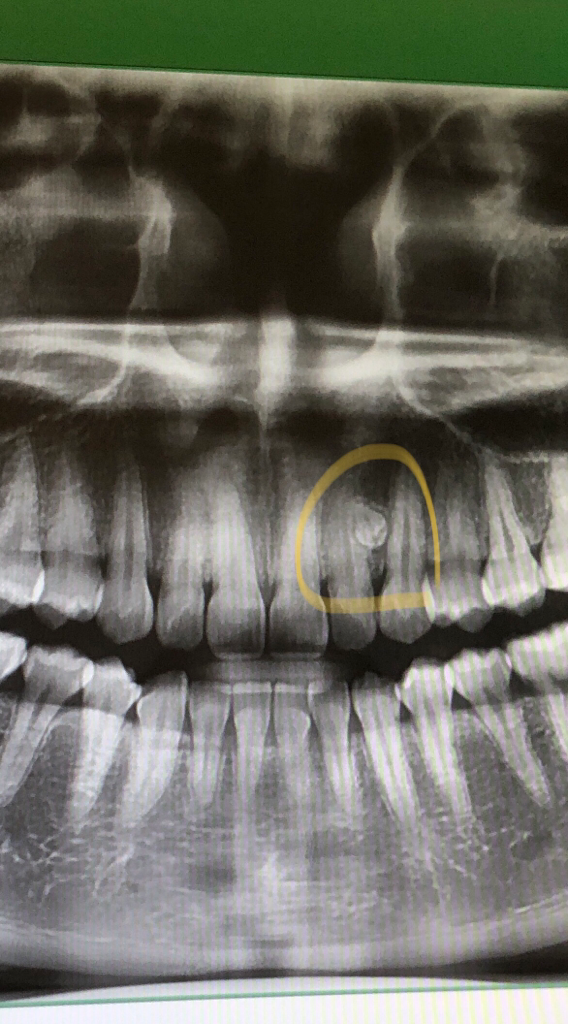

사진상 과잉치 꼭 빼야하나요?

이번에 사랑니빼면서 찍은 x레이 사진입니다

사진 상 과잉치 꼭 빼야하나요? 아니면 그대로 둬도 되나요?

사진 상 보이는 과잉치는 발치를 하시는 것이 좋으며

발치를 하는것은 많이 힘들진 않습니다.

과잉치의 정확한 위치관계파악을 위해 ct사진을 찍어보면 좋습니다

일단 과잉치가 위치상 정상치아와 근접하다면 정상치아의 뿌리를 흡수시킬수 있으며 과잉치와 함께 물혹이 형성될 수 있으며 이런 경우 주변 뼈가 녹게 됩니다

사진에 보이는 과잉치는 크게 문제가 되진 않을것같습니다. 특별한 이유가 없으면 발치를 안하셔도 될것같습니다.

사진상 과잉치아가 기존주변의 치아의 뿌리를 손상시키고 영향을 주고 있는 것으로 보이기에 이 경우 발치를 하는 것을 권합니다.